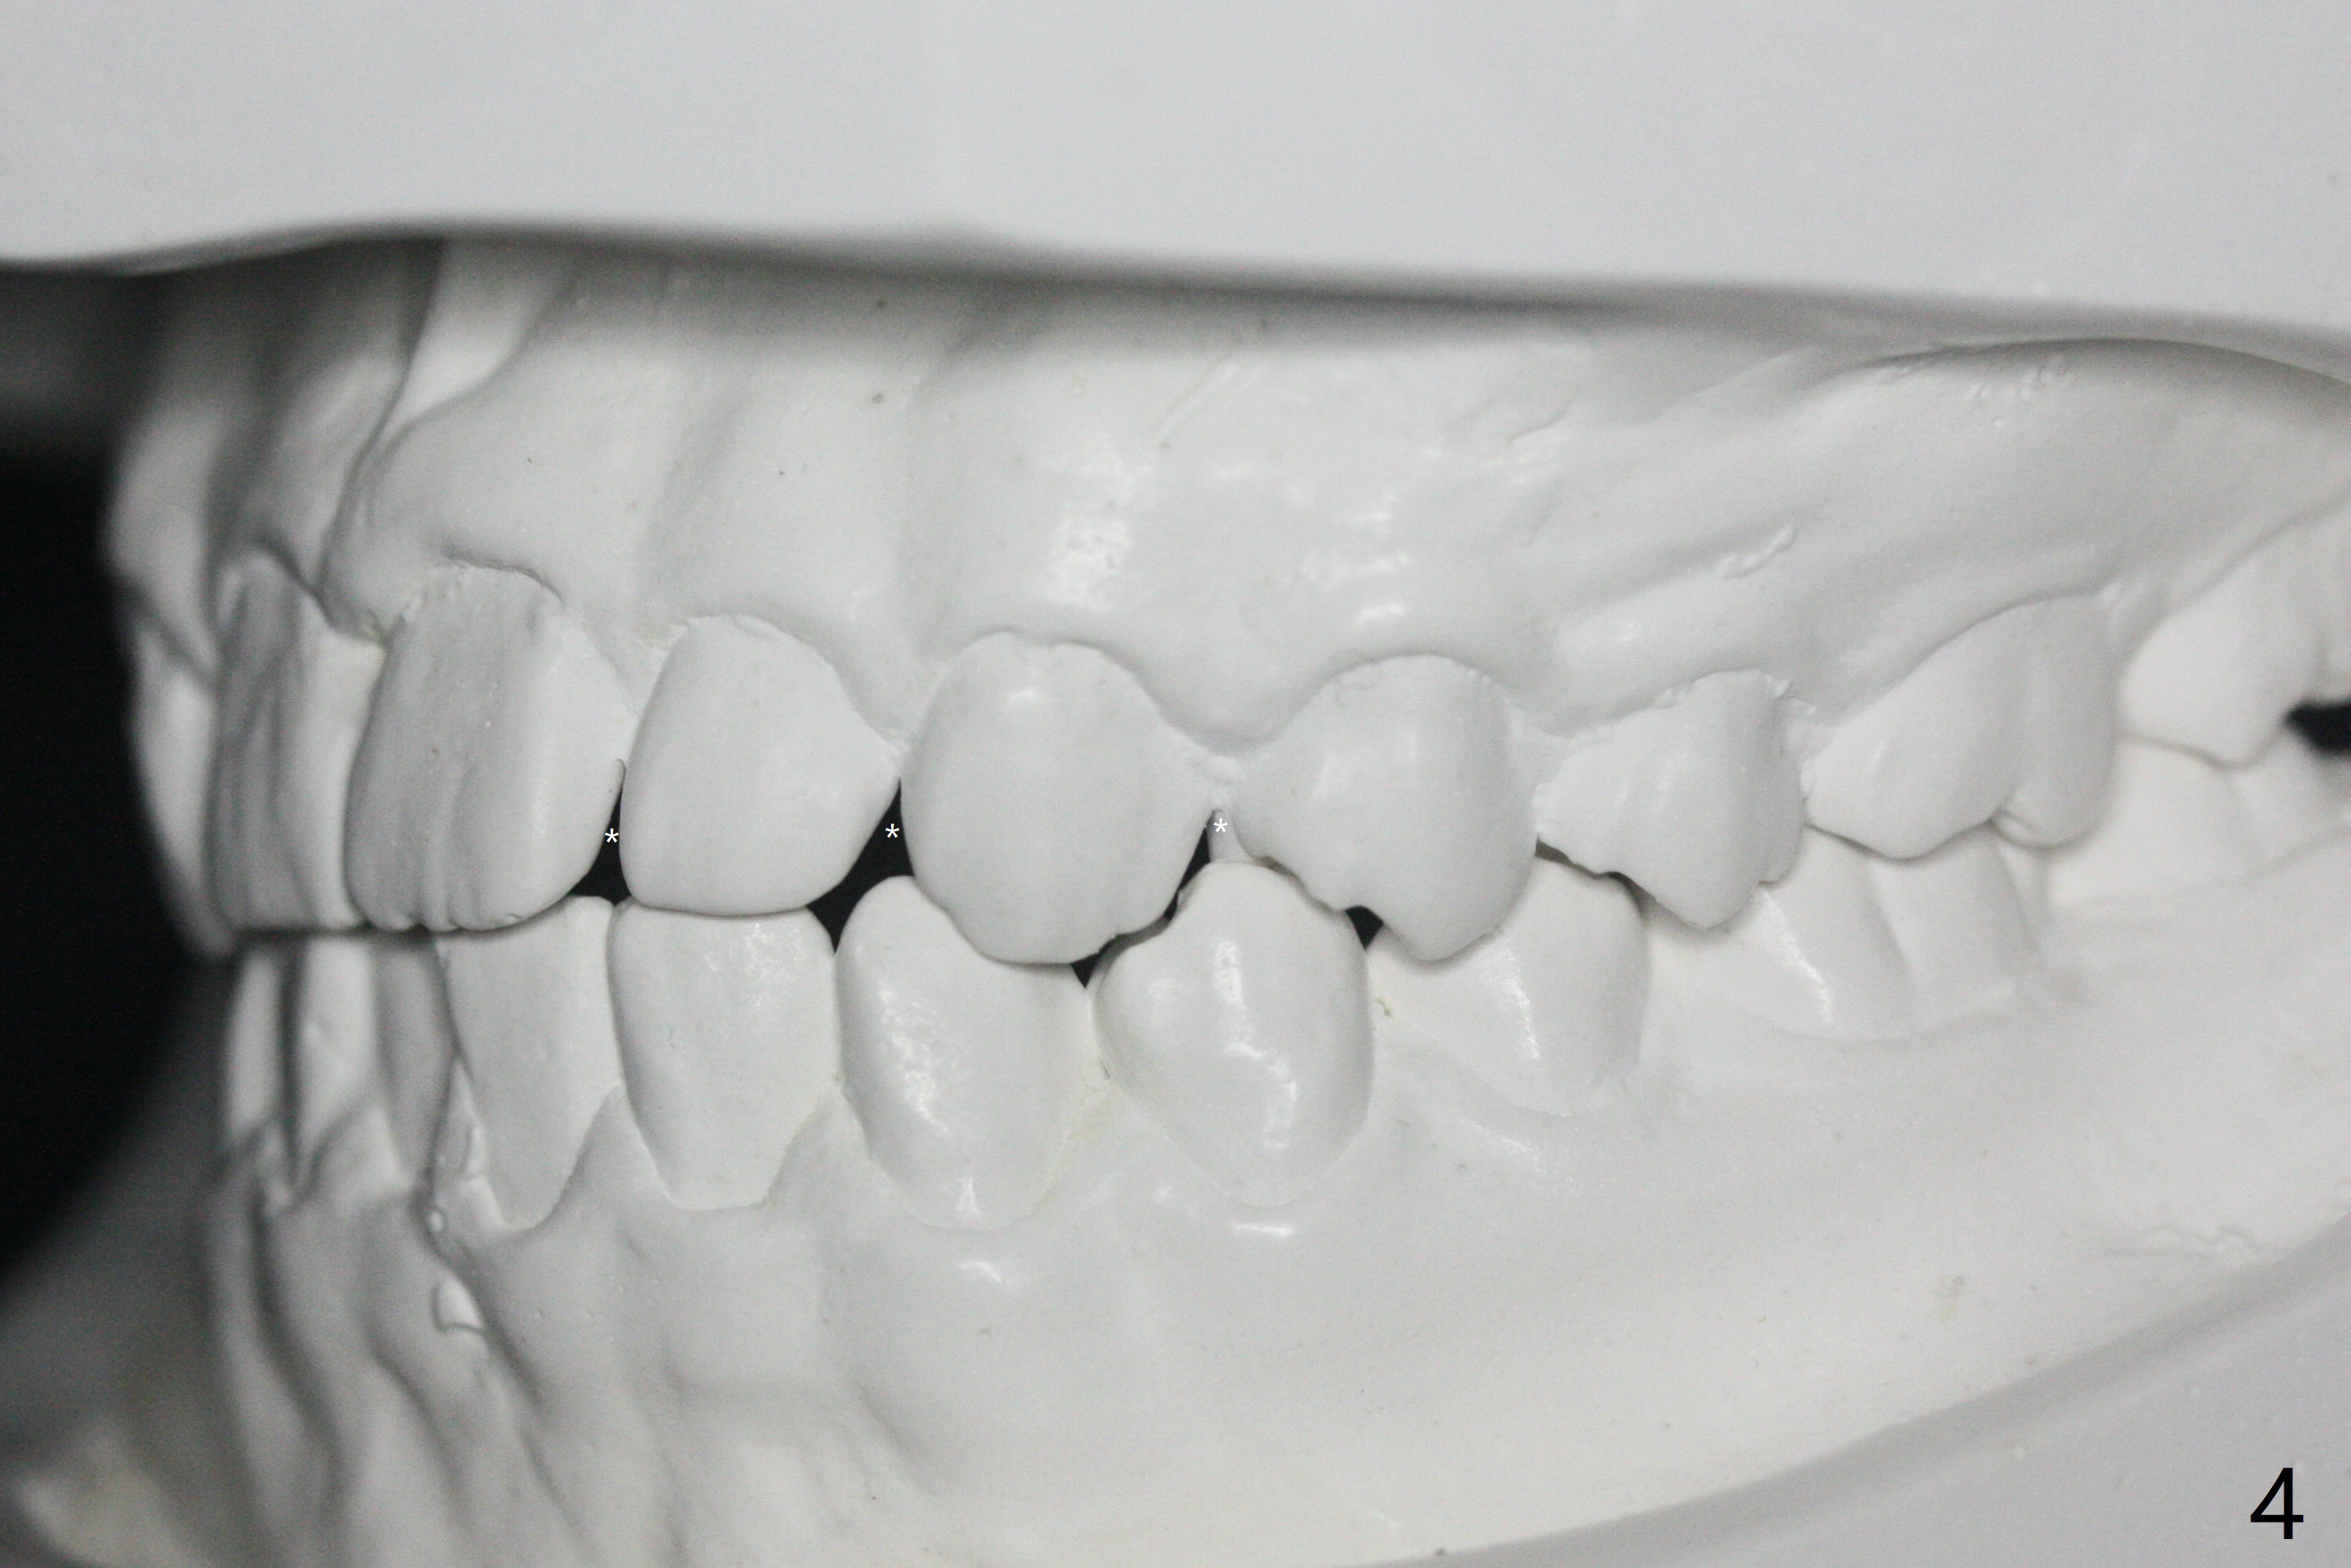

A 15-year-old man finishes orthodontic treatment for congenital missing lateral in 13 months. Molar Class I relationship remains the same (Fig.1,2,4,5). The upper diastemata mesial to 4s (Fig.4,7") close with correction of the upper midline deviation (Fig.2'-4'). The kid is unpleased with the elongated UR1 (Fig.2',3'). In fact it is a preexisting condition (Fig.2 arrow, 2"), but bracket placement at UR1 should have been overcorrected (incisal placement, Fig.3"). The intrusion should be done (Fig.4") before closure of the diastemata, since anchorage may be weakened when the separation between UR1 and 3 increases by using open coil spring. To prevent immediate relapse of the diastema between the upper central incisors, a fixed retainer is placed lingual before debracketing (Fig.6,6',6").